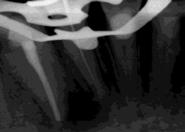

Una vez finalizada la cirugía se realiza una radiografía periapical con paralelizador que será la que se utilice como punto de partida. Los pacientes acuden posteriormente para la realización de radiografías periapicales de control, tomadas con la misma técnica, y sobre estas radiografías se realizan las mediciones necesarias para comprobar la estabilidad y pérdida ósea crestal de los implantes. La medición de la pérdida ósea marginal se realizó en la última radiografía periapical realizada con posicionador de seguimiento. Una vez obtenida la radiografía en formato digital es calibrada mediante un software específico (Digora for Windows,

SOREDEX Digital Imaging systems) a través de una longitud conocida en la radiografía como el implante dental. Una vez introducimos la medida de calibración, el programa informático realiza un cálculo basado en esta medida para eliminar la magnificación, pudiendo realizar mediciones lineales exentas de este error. La pérdida ósea crestal fue medida en 2 puntos: mesial y distal de cada implante.

Figura 1. Localicación, diámetro y longitud de los implantes incluidos en el estudio.

Fueron reclutados 8 pacientes en los que se insertaron 13 implantes que cumplieron con los criterios de inclusión previamente establecidos. De ellos, 3 fueron hombres y 5 mujeres con una edad media de 74.8 años (+/- 13.7). Ningún paciente era fumador y como patologías sistémicas asociadas, 2 pacientes refirieron hipertensión en tratamiento farmacológico. La posición dental más frecuentemente restaurada fue para la zona de 14, 34, 35 y 45 con un 15.4% para cada una de ellas. El resto de posiciones: 15, 24, 25, 44 y 46 tuvieron una frecuencia de 7.7%. La longitud de los implantes estudiados fue de 6.5 mm en el 69.2% de los casos y de 5.5 en el 30.8% restante. El diámetro de los implantes osciló entre 2.5 mm (23.1%), 3 mm (30.8%) y 3.3 mm (46.2%), presentando todos ellos una plataforma de

3 mm. La distribución del diámetro, longitud y posiciones de los implantes estudiados se muestran en la Figura 1